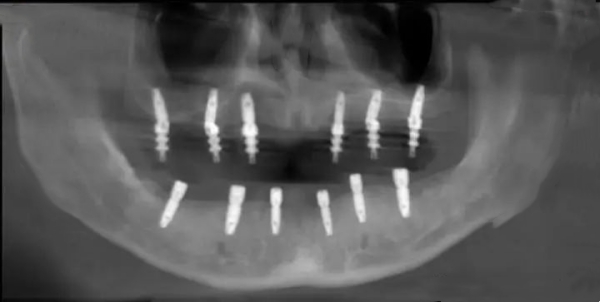

3. 種植牙類(lèi)(限時(shí)優(yōu)惠):

• 韓國(guó)品牌種植體:6800元起/顆

瑞士品牌種植體:9800元起/顆

全口種植方案:面議

2. 種植牙限時(shí)優(yōu)惠:

優(yōu)惠期間種植牙價(jià)格較平時(shí)下調(diào)15% - 20%,包含韓國(guó)和瑞士多個(gè)有名品牌種植體。優(yōu)惠涵蓋從檢查到修復(fù)的完整流程,確保價(jià)格透明。